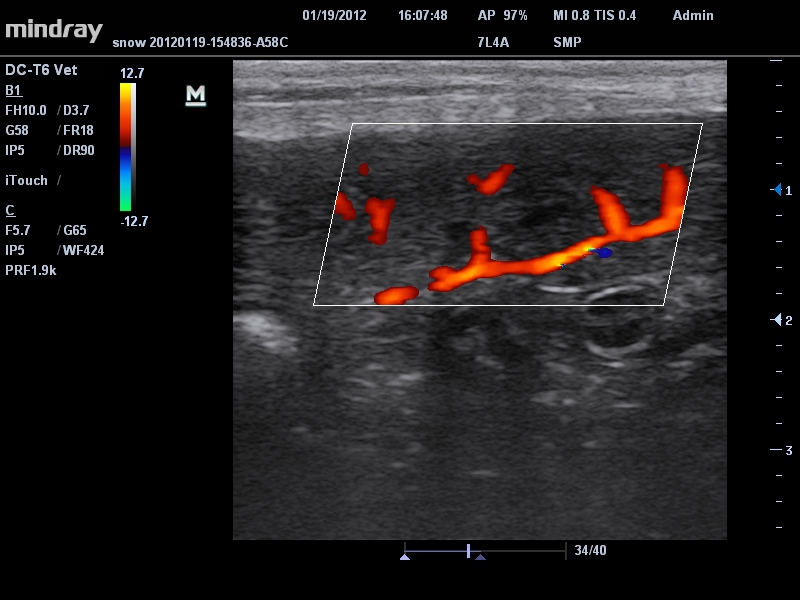

• B-Steer™ / iNeedle™: Функция маневрирования ультразвукового луча, улучшающая видимость иглы, нервных волокон и мелких сосудов.

• Режимы сканирования: B/M/CFM/PDI/Направленный PDI/PW, HPRF, Тканевая гармоника, М- и цветной М-режим.

• Линейный ультразвуковой датчик Mindray 7L4A

• Высокочастотный линейный датчик 38 мм Mindray l14-6NE